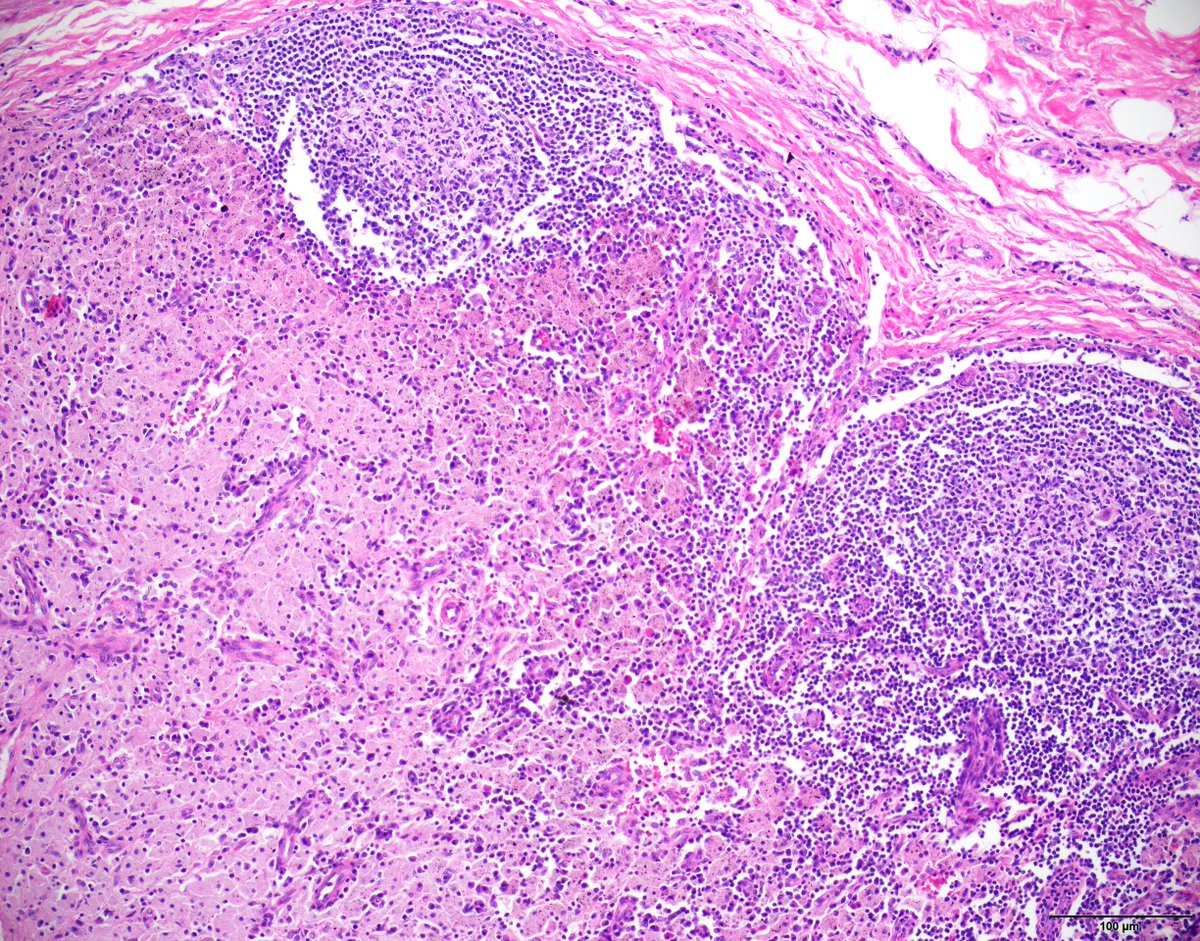

Unicentric Castleman disease-plasma cell variant:Preserved overall lymph node architecture and marked plasmacytosis in interfollicular areas,with a subset germinal centers showing regressive changes reminiscent of Castleman disease-hyaline vascular variant #Hemepath #HemepathMDA

SibaElHussein's tweet image. Unicentric Castleman disease-plasma cell variant:Preserved overall lymph node architecture and marked plasmacytosis in interfollicular areas,with a subset germinal centers showing regressive changes reminiscent of Castleman disease-hyaline vascular variant #Hemepath #HemepathMDA